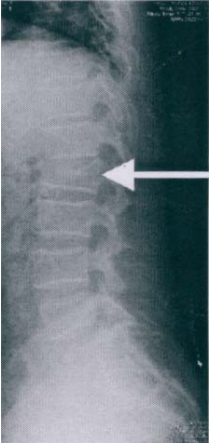

57 附圖箭頭所示,X 光診斷為第幾椎壓迫性骨折?

(A)第十二胸椎 (B)第一腰椎 (C)第二腰椎 (D)第三腰椎